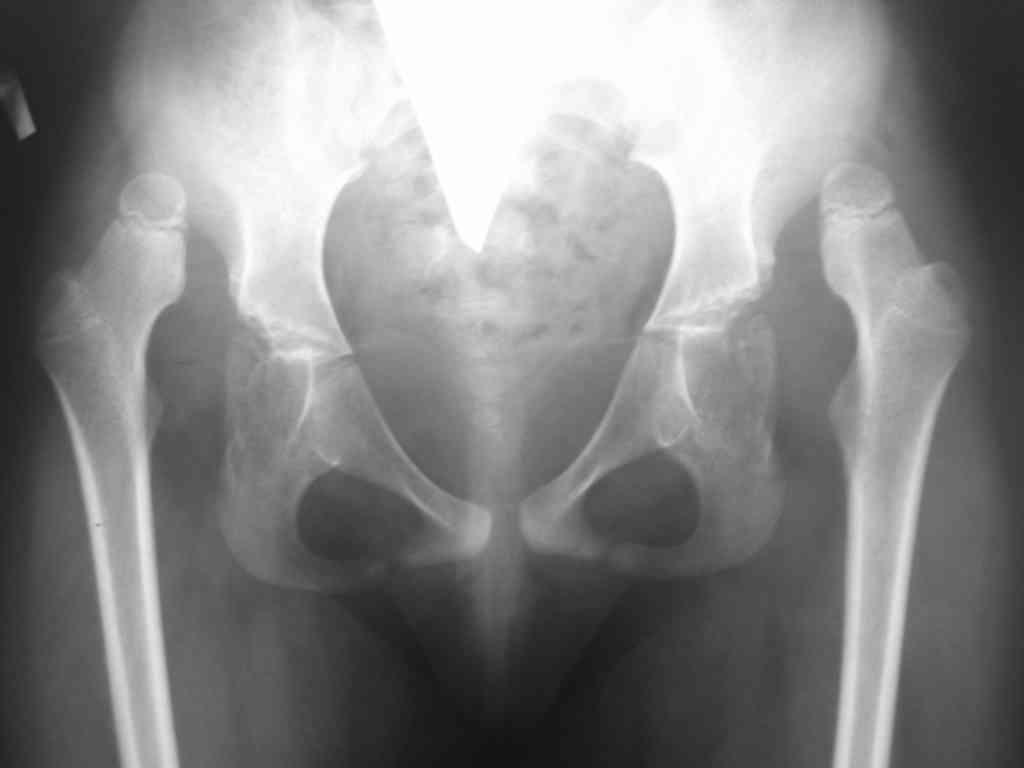

Обратились родители 7 летней девочки(1999г) с диагнозом:артрогрипоз, рецидивирующая двусторонняя косолапость, двусторонний высокий вывих бедер.

Наблюдается и лечится с 1.3 лет в детском ортопедическом институте имени Г.И.Турнера МЗ РФ Санкт-Петербург.В возрасте 1.3 года выполнены операцмм Штурма-Зацепиан по поводу двусторонней косолапости. По поводу рецидива косолапости 14.07.2004г операция Штурма-Зацепина справа + корригирующая лавсанопластика и 30.08.2004г операция Штурма-Зацепина слева + аппарат Илизарова; 29.09.2004г аппарат внешней фиксации удален на левой стопе+ корригирующая лавсанопластика левой стопы. В настоящее время больная передвигается в ортопедической обуви, рецидива косолапости нет. Родителей беспокоят состояние тазобедренных суставов-в институте им. Г.И.Турнера от вправления вывихов бедренных костей воздержались:обяснения докторов следующее: после вправления бедренных костей движения бедер может резко ухудшиться и больная не сможет себя обслуживать. Предлагают после завершения роста костей произвети тотальное эндопротезирование, а пока ждите.....И вот родители спрашивают.... да и я тоже.. как быть.. возможни ли низведение бедренных костей через, примерно 10-12 лет без последствий для нижних конечностей. А может кто из детских ортопедов и возмет девочку на лечение....?Заранее блогадарен..Снимки тазобедреннх суставов прилагаются.